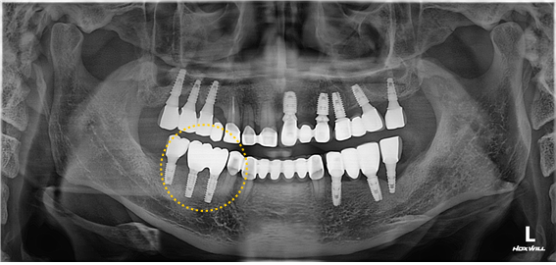

임플란트#45, 46 발치 및 뼈이식을 동반한 임플란트 식립 케이스

치료기간 : 2024. 03. 11 ~ 2024. 06. 20

상기 환자분은 ‘치아우식’으로 내원을 하셨습니다.

타원에서 한 임플란트를 보면 마진이 맞지 않고 들쑥날쑥한걸 볼 수 있죠.